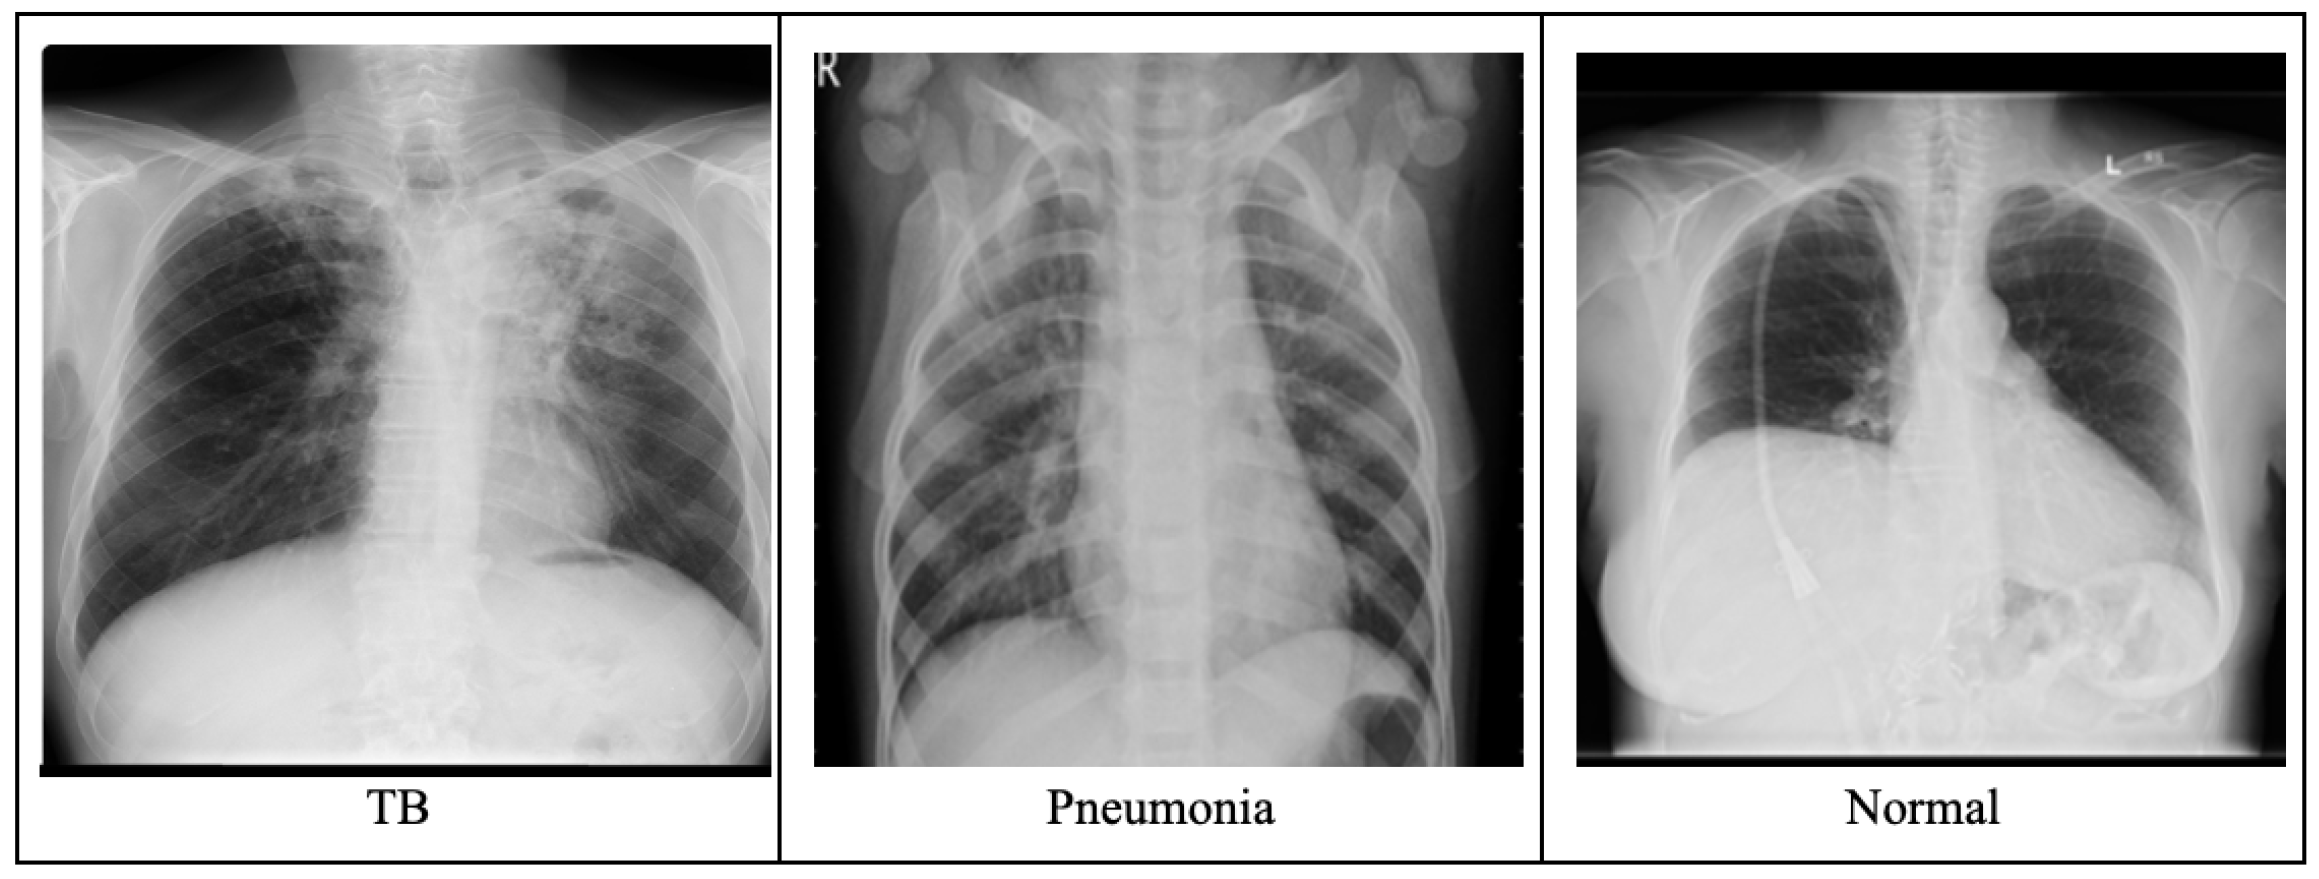

We utilized two datasets in this study. ChestXray-14 Dataset: A publicly available dataset with 112,120 chest X-ray images labeled for 14 thoracic diseases, collected in the United States (US), and organized by the National Institutes of Health (NIH). This dataset was used as the source domain. Nigerian Chest X-ray Dataset (Nigeria CXR): Collected from Aminu Kano Teaching Hospital in Nigeria, this dataset consists of 6345 chest X-ray images labeled into four classes: Pneumonia, COVID-19, Tuberculosis (TB), and Normal. This dataset was used as the target domain.

Figure 1 shows sample images from the dataset. Both datasets were annotated by radiologists and pre-processed to ensure consistency in image size and quality. We applied standard image augmentation techniques such as rotation, flipping, and contrast adjustment to increase the diversity of the training data and improve the model’s robustness to variations in image quality and acquisition settings.

Figure 1.

Sample X-ray images from dataset.